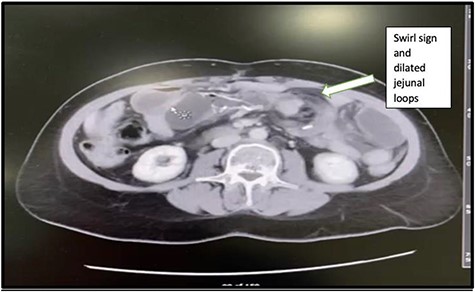

A 48-year-old-lady presented to our emergency department with 3 days history of colicky abdominal pain. The patient had a background history of LRYGB that was done 2 years ago and a history of laparoscopic internal hernia repair that was done in November 2020. On examination, she was vitally stable (P: 88, BP: 120/86, T: 37.0), with an abdominal examination of mild tenderness at the left upper quadrant region. Her initial laboratory investigations were WBC: 9.6 109g/l, HB: 9.0, PLT: 275, kidney function test (creatinine: 72, urea: 4.5) and lactic acid was normal: 0.8 (range: 0.5–2.2). CT scans of abdomen and pelvis showed mesenteric vessels swirl and dilated small bowel loops with the transitional zone at the jejunal anastomosis (Fig. 5). The patient was improving with intravenous fluids; thus, the initial decision was to conserve. However, 2 days later, symptoms increased. Repeat CBC and lactic showed a marked increase in WBC and lactic acid (12.8 109g/l, 7.8), respectively. Therefore, the patient was shifted to the operating room.